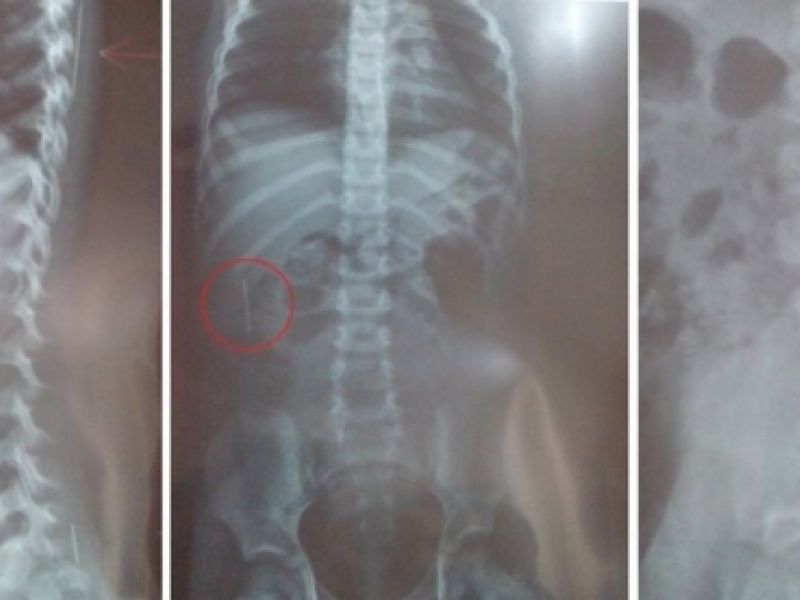

Jovem é suspeito de espetar agulhas na enteada durante ritual de magia negra